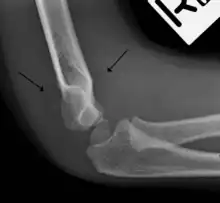

Fat pad sign

The fat pad sign, also known as the sail sign, is a potential finding on elbow radiography which suggests a fracture of one or more bones at the elbow. It is may indicate an occult fracture that is not directly visible. Its name derives from the fact that it has the shape of a spinnaker (sail).[1] It is caused by displacement of the fat pad around the elbow joint. Both anterior and posterior fat pad signs exist, and both can be found on the same X-ray.

The fat pad sign is invaluable in assessing for the presence of an intra-articular fracture of the elbow. An anterior fat pad is often normal. However a posterior fat pad seen on a lateral x-ray of the elbow is always abnormal. The patient will be unable to flex their elbow and requires orthopaedic input.[2]

The posterior fat pad is normally pressed in the olecranon fossa by the triceps tendon, and hence invisible on lateral radiograph of the elbow.[3] When there is a fracture of the distal humerus, or other pathology involving the elbow joint, inflammation develops around the synovial membrane forcing the fat pad out of its normal physiologic resting place. This is visible as the "posterior fat pad sign" and is often the only visible marker of a fracture, particularly in the pediatrics population.